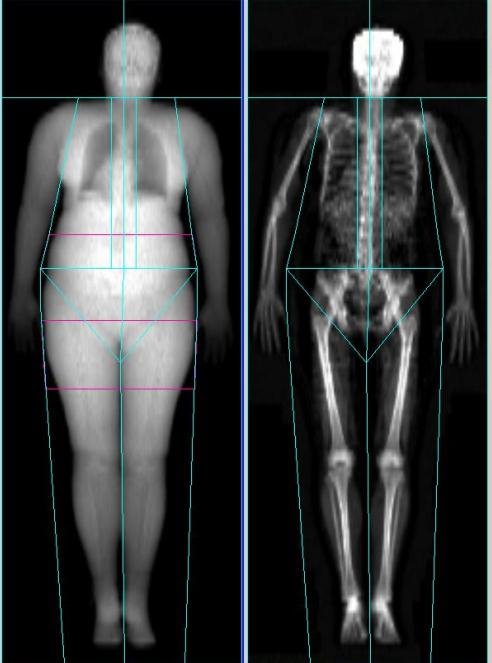

Термин «остеоденситометрия» -- сборное сочетание латинских слов osteo—«кость», densitas – «плотность», metria – «мерить». Исследование предназначается для измерения толщины костного слоя с помощью лучей ультразвука или рентгена. При остеопорозе показатели денситометрии изучают на определенных этапах терапевтического курса лечения заболевания.

- Ультразвуковое (эходенситометрия) – вычисление волновой скорости ультразвука после проникновения через ткани разной плотности. Применяется для детекции толщины кости. Недостаток процедуры – возможность выявления только начальных остеопоротических изменений, когда потеря минерализации не превышает 4%;

- Рентгеновское – основан на регистрации прохождения рентгеновского луча через плотные ткани. Диагностирует снижение плотности до 25%. Радиационное облучение исследуемой области минимально, поэтому обследование можно проводить много раз в год.

Рентгеновское исследование на остеопороз денситометрией выявляет изменения в нескольких зонах:

- Верхняя часть бедренной кости;

- Поясничный отдел позвоночника;

- Любые части скелета;

- Лучезапястный сустав.

Современные рентгенологические денситометры обеспечивают низкую дозу облучения за счет использования небольших трубок, испускающих тонкий луч, направленный непосредственно в нужную область.

В заключение расскажем о том, что анализ на остеопороз может быть проведен путем классической рентгенографии с абсорбциометрией, ультразвуковой костной денситометрии. В последнее время активно рекламируется способ КТ-денситометрии. Достоинством исследования является создание трехмерного изображения, более высокая информативность по сравнению с ультразвуковым аналогом. Повсеместное применение обследования ограничено ионизирующим облучением пациента. С помощью 3D-моделирования удается отследить локальные участки остеопороза, возникающие при некоторых болезнях. В пожилом возрасте прослеживается распространенная деминерализация костной ткани, изменения в которой лучше отслеживать рентгеновскими денситометрами с абсорбциометрией (из-за высокой достоверности и малого облучения тканей).